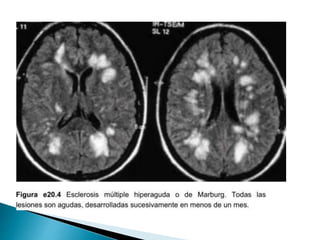

 Esclerosis cerebral difusa de Schilder.

 La variante de Marburg.

 Características de las lesiones

desmielinizantes en 95% de los casos:

◦ Hipointensas T1.

◦ Hiperintensas T2.

◦ Ovoides / forma de anillo abierto.

◦ Diámetro de 3 a 6 mm.

◦ Bordes brumosos mal definidos.

◦ Reforzamiento en T1 GDTPA.

 Características delas lesiones desmielinizantes en 95% de los casos: ◦ Hipointensas T1. ◦ Hiperintensas T2. ◦ Ovoides / forma de anillo abierto. ◦ Diámetro de 3 a 6 mm. ◦ Bordes brumosos mal definidos. ◦ Reforzamiento en T1 GDTPA. Enfermedades desmielinizantes del sistema nervioso central O. Fernández, V. E. Fernández y M. Guerrero - Medicine. 2015;11(77):4601-9